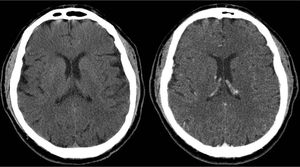

Regarding a conversation on Facebook: 1) Iodine contrast is not visible on MRI. 2) High-dose Gadolinium contrast may be visible on CT. Fig High-dose Gd seen on CT. On left, noncontrast head image. On right CT obtained after intravenous administration of 60 cc of gadopentetate dimeglumine (Magnevist) shows weak enhancement of choroid plexus and vessels. https://lnkd.in/dPhTMdK So, if a patient needs a CT with contrast and a MRI with contrast, CT examination should be done first.